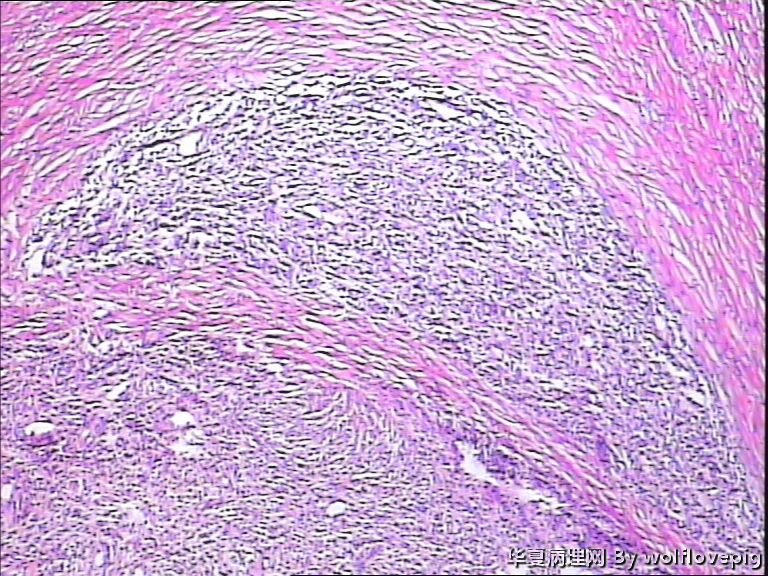

请教!子宫肌瘤。

37y,肌壁间可见多个小结节0.2~0.8cm。